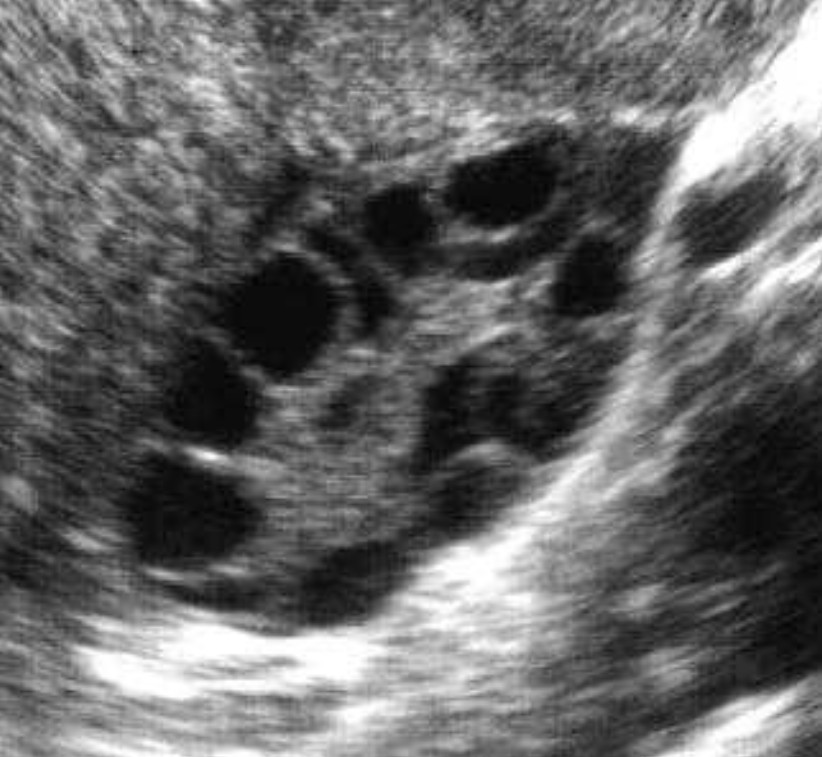

Buồng trứng đa nang (tiếng Anh là Polycystic Ovary Syndrome – PCOS) là một dạng rối loạn nội tiết tố thường gặp ở phụ nữ trong độ tuổi sinh sản. Bệnh gây nhiều tác động lên buồng trứng khiến chu kỳ kinh nguyệt bị rối loạn, tăng nồng độ nội tiết tố nam, dẫn đến hình thành nhiều nang nhỏ bên trong buồng trứng. Có khoảng 2,2 – 26,7% phụ nữ trong độ tuổi sinh sản (15 – 44 tuổi) mắc hội chứng đa nang buồng trứng. Và nhiều người trong số họ không biết mình mắc bệnh nên không điều trị sớm dẫn đến nhiều biến chứng.

- Buồng trứng có nhiều nang nhỏ.

- Siêu âm vùng chậu thường chỉ được chỉ định nếu nồng độ androgen trong huyết thanh hoặc mức độ nam hóa gợi ý một khối u buồng trứng. Siêu âm qua đường âm đạo thường không được sử dụng để chẩn đoán hội chứng buồng trứng đa nang ở trẻ em gái vị thành niên vì nó phát hiện hình thái đa nang ở < 40% số trẻ em gái và, được sử dụng đơn lẻ, không dự đoán sự hiện diện hoặc phát triển của hội chứng buồng trứng đa nang.